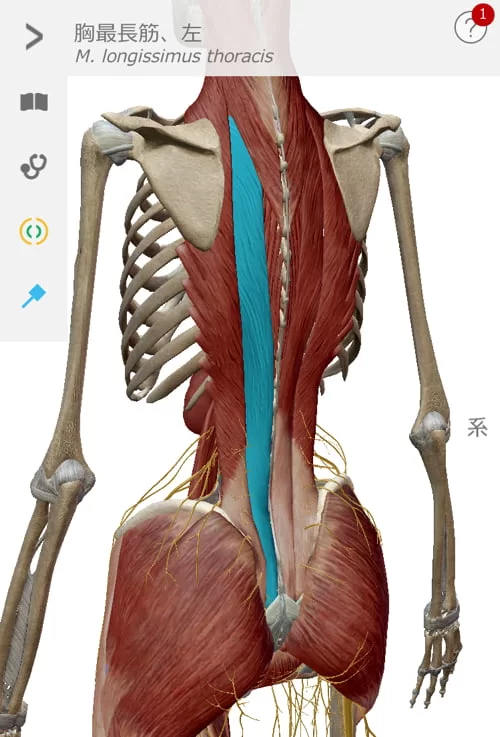

今回のお客様はちょうどこんな感じで背中と太腿の筋肉が硬直していて

腰を上からも下からも引っ張っている状態。

施術はまず背中の硬直を解いていくことから行いました。

脊柱起立筋群。